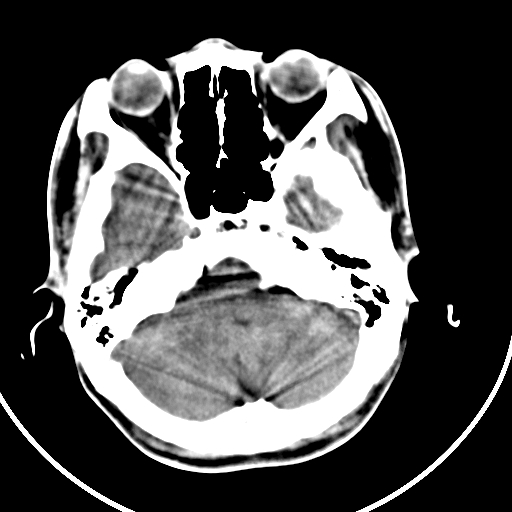

颅骨凹陷性骨折并压迫脑组织致大脑镰下疝!

硬膜外血肿机化

如果是骨折,外板正常内板这么明显凹陷,请问这样的骨折是怎样形成的?形成的机理是什么?有没有可能形成?

硬膜外血肿伴包膜钙化

左侧额部硬膜外血肿机化、骨化。

左侧额部硬膜外血肿机化、骨化